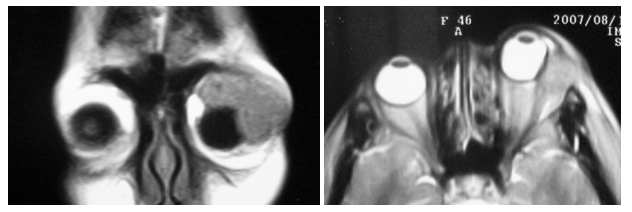

患者全身情况尚可,未见其他病变。眼部检查:右眼视力1.0,外眼和眼底检查未见异常;左眼视力指数/20 cm,眼球突出并向鼻下方移位,眼球突出度9 mm,眼球上转不能,内、外、下转受限严重,眼球运动受限,上眼睑高度红肿且有压痛,睑裂闭合不全,结膜高度充血水肿,角膜上皮有点片状灰白色混浊,虹膜正常,瞳孔反射(+),晶状体透明,眼底窥不清。左眼眶外上缘可触及质地较硬的肿物、约呈2 cm × 3 cm,边界不清,有压痛;眶压(++) (图1)。彩色超声波检查显示左眼眶外上方占位性病变,约呈3.08 cm × 1.81 cm,形态不规则,边界不清晰,内回声不均匀,有丰富血流信号,眼球壁受压明显。复查眼眶CT,显示左眼眶泪腺增大,眼眶内不规则团块影,边界欠清,内部密度不均,增强后可见均匀强化,邻近外侧眶骨壁有虫蚀状缺损,眼球受压(图2)。当地MRI显示,眶外上泪腺区椭圆形占位,T1WI为中低信号,T2WI为中高信号(图3)。结合患者的临床表现和天津市眼科医院CT检查结果,考虑为左眼眶部泪腺区占位性病变,不能排除恶性肿瘤。2007年10月12日,患者于全身麻醉下行左眼眶肿物切除术。术中发现眼眶上方充满灰白色肿物,无明显包膜,并侵及提上睑肌和眶上神经。

20230626161642_4157.png

图3 MRI图像显示左眼眶外上方肿物,T1中低信号,T2中高信号

Figure 3 MRI showing mass with iso/hypo-intensity on T1WI, and iso/hyper-intensity on T2WI in the superotemporal aspect of the orbit